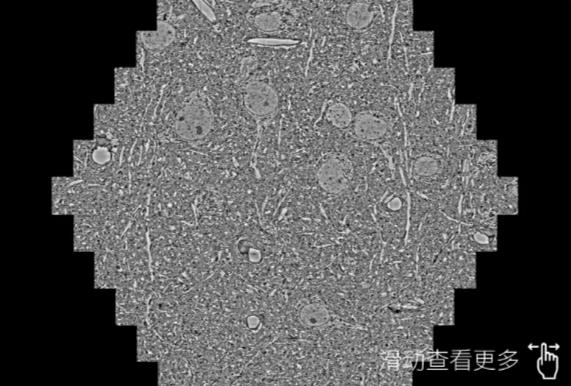

鼠脑切片。左图使用雅安蔡司雅安扫描电镜MultiSEM706对165μmx143pm面积区域成像,耗时仅需1.5秒。右图为鼠脑切片中30μm区域放大效果。样品由芝加哥大学B.Kasthuri提供。